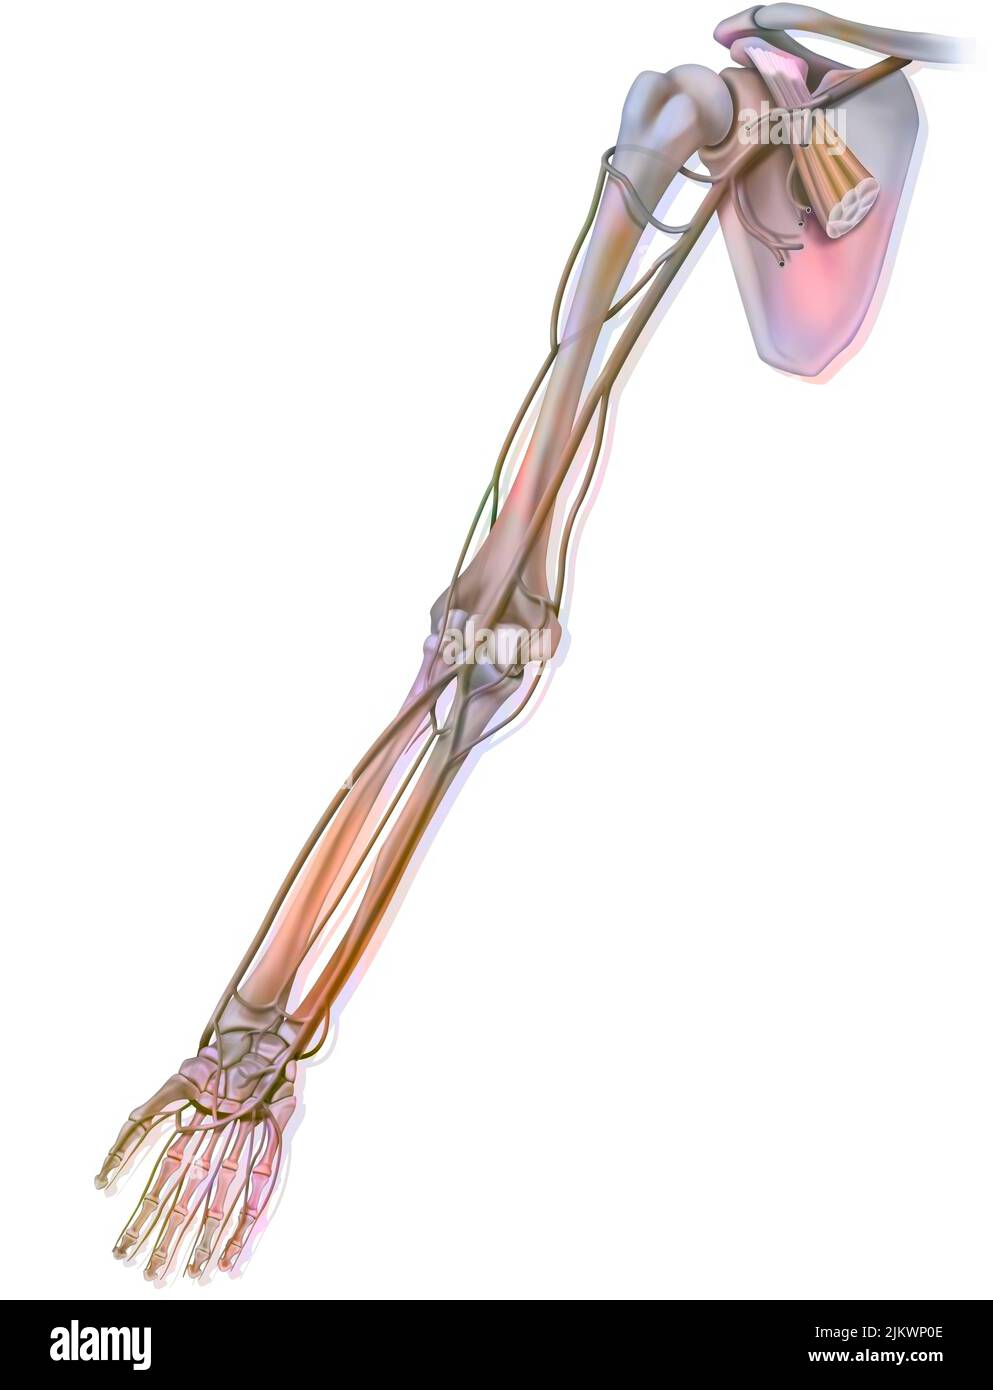

RMJE7CWP–Der Plexus brachialis ist ein Nervennetz im Nacken- und Schulterbereich, das für die motorischen und sensorischen Funktionen der oberen Extremität von wesentlicher Bedeutung ist. Das Bild zeigt den Plexus brachialis an seiner anatomischen Position.